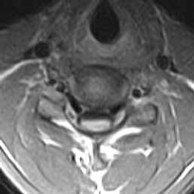

• There is a loss of the normal ventral bulge (flattened) of the cervical spinal cord, more so to the right over the C5 to C7 levels. Hyperintense signal, best appreciated on the GRASS axial images is seen within the cervical spinal cord, ventrally (anterior horn cells) over these levels.